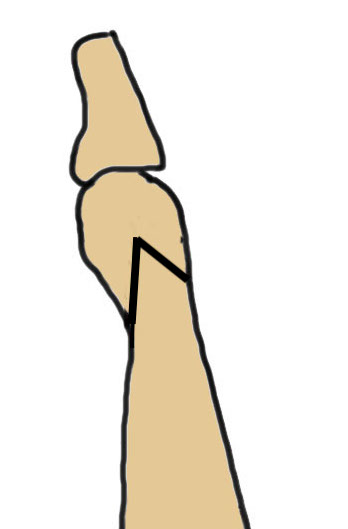

Coughlin Classification

| Type I | Type II | Type III |

|---|---|---|

| Prominent lateral condyle 5th metatarsal head | Lateral bowing of 5th metatarsal |

Increased 4/5 intermetatarsal angle Normal 5 degrees 5th metatarsal straight |

| Lateral condylectomy | Osteotomy | Osteotomy |

Lateral bowing of 5th metatarsal

Increased intermetarsal angle (IMA). Normal is 5 degrees

Osteotomy

Distal

- Weil distal sliding osteotomy

- Chevron osteotomy